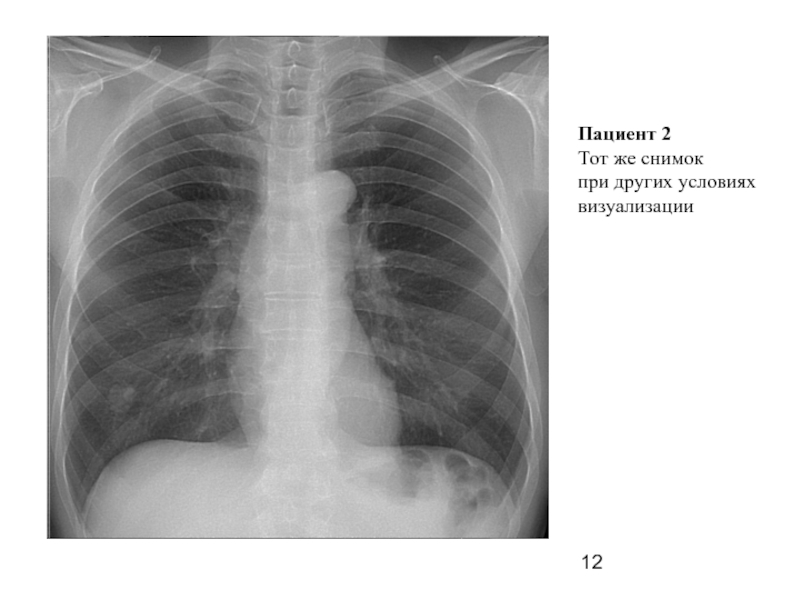

Слайд 12Пациент 2

Тот же снимок

при других условиях

визуализации

Слайд 11Пациент 2

Описание:

Отрицательная динамика в виде появления в S-4 справа округлой тени

высокой интенсивности с неровными четкими контурами, диаметром 18 мм, с неотчетливой

дорожкой к корню. Во 2 межреберье небольшие неинтенсивные очаги.

Плевральные синусы свободны. Сердечная тень не расширена. Склероз аорты.

Заключение:

Дифф. диагноз между периферическим процессом (МТ?) и туберкуломой S-4

справа.

Вторичные очаги в верхней доле справа. Направить на R-графию ОГК, затем в ООД, к фтизиатрам.